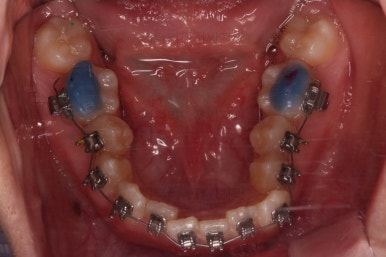

장치를 처음 부착한 사진입니다.

이번 환자분은 특징적으로 윗니의 장치와 아랫니의 장치가 다르죠.

윗니는 좀 더 심미적인 세라믹으로 선택하셨고 아랫니는 비교적 저렴하고 부피가 약간 작고 튼튼한 메탈로 진행했습니다.

그래도 됩니다.

심지어는 같은 회사 제품이 아니더라도 적절하게 세팅을 고려하면 섞어 사용하는 것도 가능하답니다.